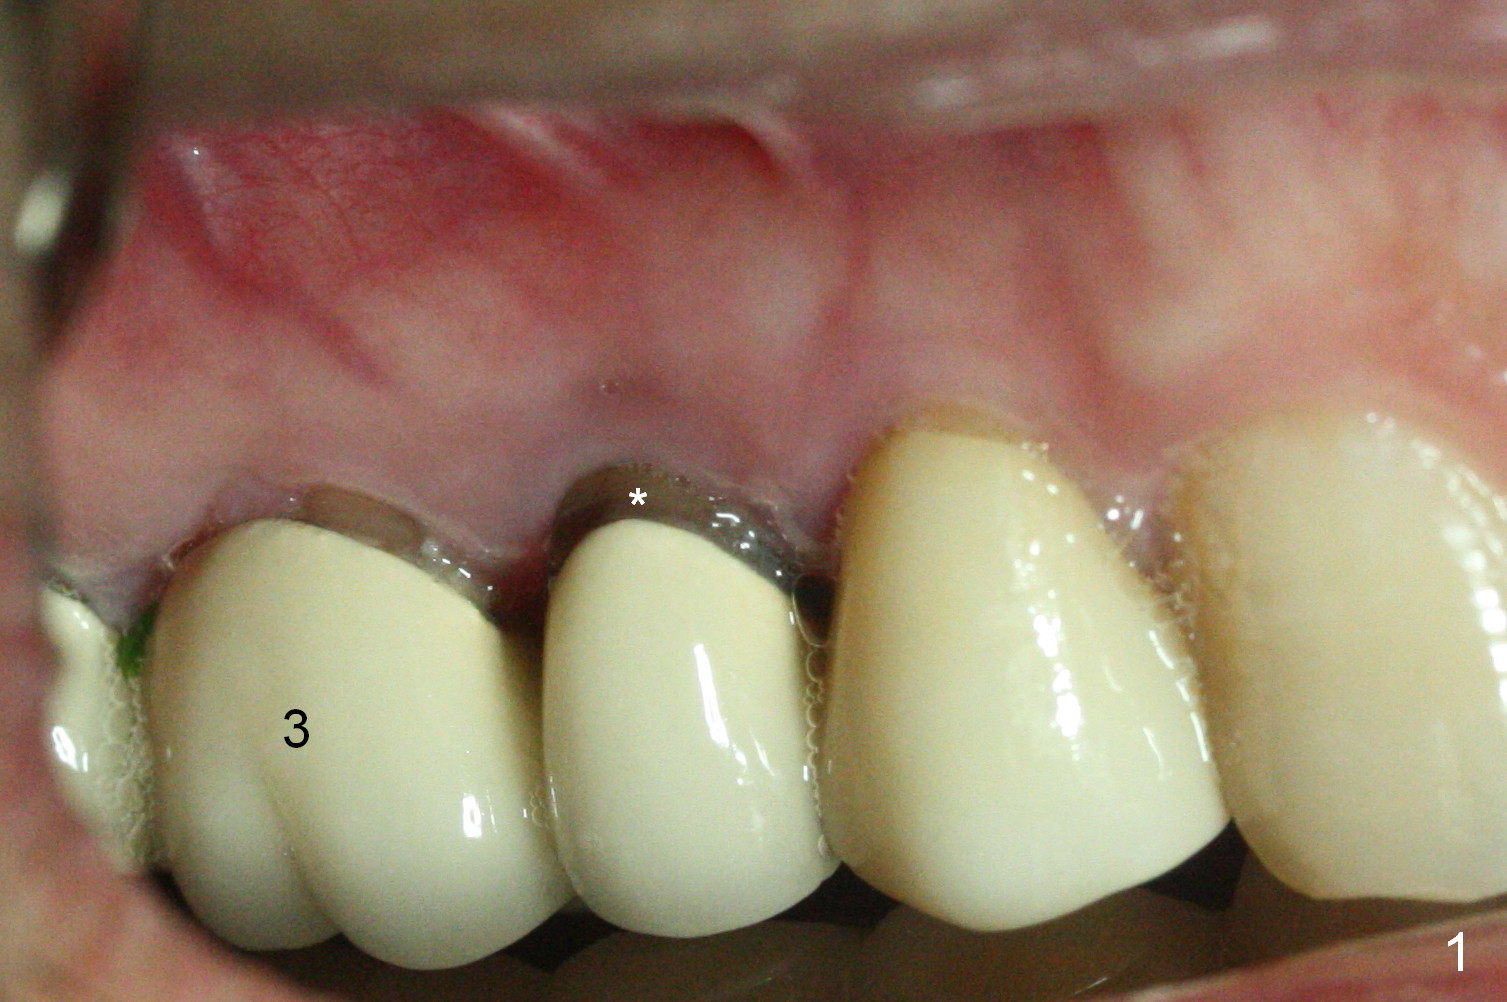

A 42-year-old man returns with chief complaint of chipped tooth at #3. Crowns at #3 and 4 are splinted (Fig.1). The tooth #4 is discolored (^). X-ray exam shows post (P) -induced Root (R) split with severe bone loss at #4 (Fig.2). To decrease periimplantitis, use an implant as narrow as possible (4 mm) and as long as apical bone allows (13 mm, IBS, Fig.3). Section the retainer at #3 and remove the tooth #4 (Metronidazole). Prepare PVS impression to record socket morphology. Magic Expanders are to be applied for osteotomy and sinus lift if possible. Finally fabricate splinted provisional at #3 and 4.